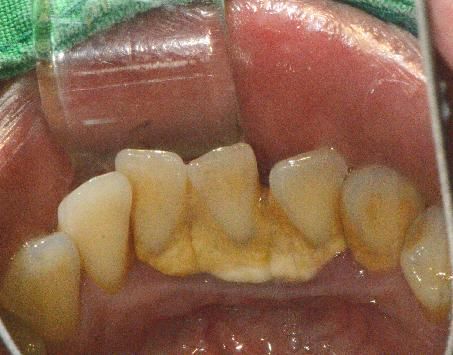

안녕하세요 목동안치과의 안상우 원장입니다.오늘은 스케일링에 대해서 알아보겠습니다.스케일링은 치아 주변의 치석을 제거해서 치주질환이 생기지 않게 해주는 술식이에요.잇몸에 염증이 생기는 원인은 치아 주변에 잔류되어 있는 이물질이 오랜시간이 지나면서 부패되기 때문입니다.피부에도 이물질이 오래 남아 있다면 피부트러블이 생기는 것과 같은 원리입니다.치아의 뿌리와 치주인대 그리고 치조골을 치주조직이라고 하고 치주조직이 건강해야 치아에 가해지는 교합력을 잘 전달할 수 있게 되어 건강한 저작기능이 가능합니다.이 사진은 잇몸에 염증이 있는 사진입니다.약간 부어 있는듯한 모습을 보이죠. 잇몸에 염증이 생기게 되면 잇몸조직이 약해지고 면역세포들이 필요하게 되어 혈액이 모이게 됩니다. 이런 상태에서 칫솔질을 하게되면 잇몸의 손상되면서 함께 출혈이 생길수 있습니다.칫솔질을 할때 출혈이 된다면 잇몸 어딘가에 염증이 있을 가능성이 높습니다.따라서 칫솔질을 할 때 피가난다면 가까운 치과에서 피가 나는 원인을 확인해야 합니다 .이런 염증이 오래 지속되게 되면 치주조직에 손실이 오게 되고 결과적으로 치아가 흔들리거나 정상적인 음식을 저작하는데 문제가 발생하게 되요.치석은 치아 표면에 있는 이물질이 침에 있는 석회화 된 물질로 단단하게 석회화 되어 있습니다.이런 치석이 있을 경우에 치아 주면에 이물질이 더 잘 저류할 수 있게 되어 잇몸에 염증을 발생시킬 수 있어요.치석은 고도로 석회화 되어 있기 때문에 일반적인 힘으로는 제거할 수가 없습니다. 치과에서 스케일링이라는 술식으로 제거해야 합니다.이것은 치과에서 치석을 제거할 때 사용하는 스케일러입니다.치석이 제거되면 이런 염증이 없어지게 되고 정상적인 잇몸으로 돌아오게 됩니다.음식을 먹고 난 다음에 생기는 이물질은 반드시 칫솔질이나 치실, 치간칫솔로 깨끗하게 제거해 주시고 그 외에 제거가 되지 않는 치석은 치과에서 제거해 주는것이 좋습니다.

충치는 산성으로 인해서 치아의 구조가 무너지는 현상입니다.충치라고 무조건 치료를 하는것이 아닙니다. 충치도 종류가 있어요충치는 정지된 충치가 있고 진행되는 충치가 있습니다.우선 건강한 치아를 한번 볼께요 이 사진은 건강한 상태의 치아 입니다.이전에 레진 치료를 받은 흔적이 있지만 충치가 없는 상태의 치아에요.이 사진은 검은색으로 보이는 부위가 충치입니다.이 사진에도 치아를 따라서 보이는 검은 것이 충치에요.충치가 생겼을 때는 보시는 바와 같이 육안으로 확인할 수 있습니다.이렇게 검은색을 띠고 단단한 형태는 정지되어 있는 충치라고 볼수 있습니다.충치가 있는데 다시 석회화 되면서 충치가 더 진행이 되지 않는것이지요.이런 충치의 경우 충치니까 치료를 해야 하는것은 맞습니다. 하지만 진행이 되지 않고 정상적으로 기능을 하기 때문에 관리를 잘 한다면 치료를 보류해볼수 있어요.이 사진에도 충치가 보입니다. 치아는 외부는 검은식이지만 내부는 갈색을 보이는데 이런 형태의 충치는 진행이 되는 충치 입니다. 이런 식의 충치는 푸석푸석하며 치아의 구조가 약해져 있습니다.이런 진행중인 충치인경우에는 빠르게 치료를 해줘야 합니다.충치가 오래 진행이 되다보면 치아의 치질이 손상되게 됩니다.충치가 생긴 부위는 방사선 사진으로도 알수있는데요.우선 정상적인 치아를 한번 볼께요.왼쪽의 치아의 머리는 하얗게 생긴 정상적인 치아입니다.다음사진은 충치가 있는 사진인데요. 두개의 치아 사이에 검은 음영이 보이는데충치가 생겼을 때는 이렇게 방사선상에 음영으로 보이게 되요이 부분이 충치에 의해서 파괴된 부분입니다이 충치가 치아안의 신경까지 진행이 되지 않으면 신경치료를 안하고 간단하게 치료할 수 있는데충치가 신경까지 진행된 경우에는 통증을 느끼게 되고 염증이 생겨서 신경치료를 동반한 보철치료를 계획해야 합니다.충치는 신경에 도달하기 전까지는 통증이 없기 때문에 진행이 많이 되고 난 다음에 병원에서 뒤늦게 확인하는 경우가 많아요따라서 평소에 관리를 잘하고 이상이 없어도 치과에서 주기적으로 검사하는 것이 좋습니다.충치는 오랜기간에 걸쳐서 생기기 때문에 충분한 관심을 가지고 관리를 해주면 생기는 것을 방지 할수 있어요그럼 여러분의 구강내에 충치가 생기지 않도록 충분한 관심을 가지고 칫솔과 치실을 이용하여 꼼꼼하게 관리를 해주세요.여러분의 치아는 소중하니까요